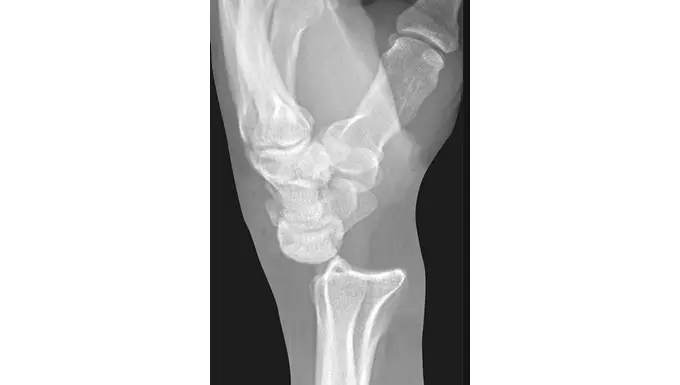

2. Perilunate Dislocation

- Surrounding bones dislocate while the lunate remains aligned

- Commonly missed on initial evaluation

Imaging

- X-rays (primary diagnostic tool)

Special radiographic signs (like disrupted alignment lines) help detect subtle dislocations.